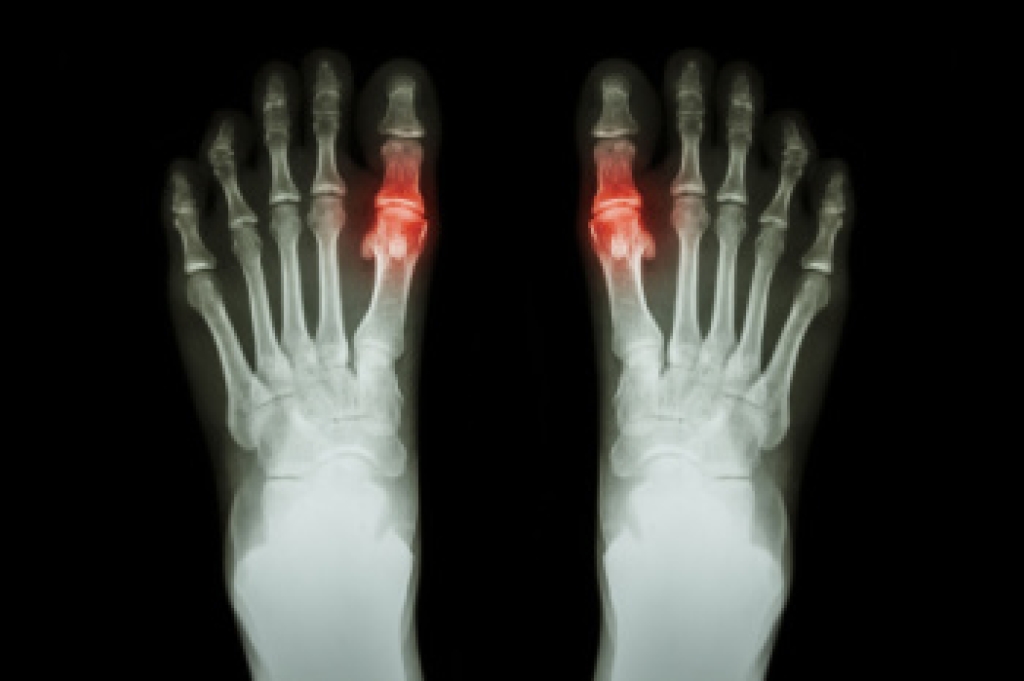

A fifth metatarsal fracture is a break in the long bone on the outside of the foot that connects to the little toe. This injury often occurs after a sudden twist of the foot, a misstep on uneven ground, or direct impact during sports. Patients usually notice sharp pain along the outer side of the foot along with swelling and bruising. Walking may become difficult, and the area can feel tender to the touch. Some fractures occur near the base of the bone and may develop slowly from repeated stress, especially in athletes or active individuals. A podiatrist begins with a careful examination of the foot and reviews how the injury occurred. X-rays are often used to confirm the fracture and determine its exact location. Treatment may include protective immobilization, limited weight bearing, and targeted exercises once healing begins. In certain cases, surgery may be recommended for proper alignment. If you think you may have a foot fracture, it is suggested that you make an immediate appointment with a podiatrist.

A broken foot is caused by one of the bones in the foot typically breaking when bended, crushed, or stretched beyond its natural capabilities. Usually the location of the fracture indicates how the break occurred, whether it was through an object, fall, or any other type of injury.